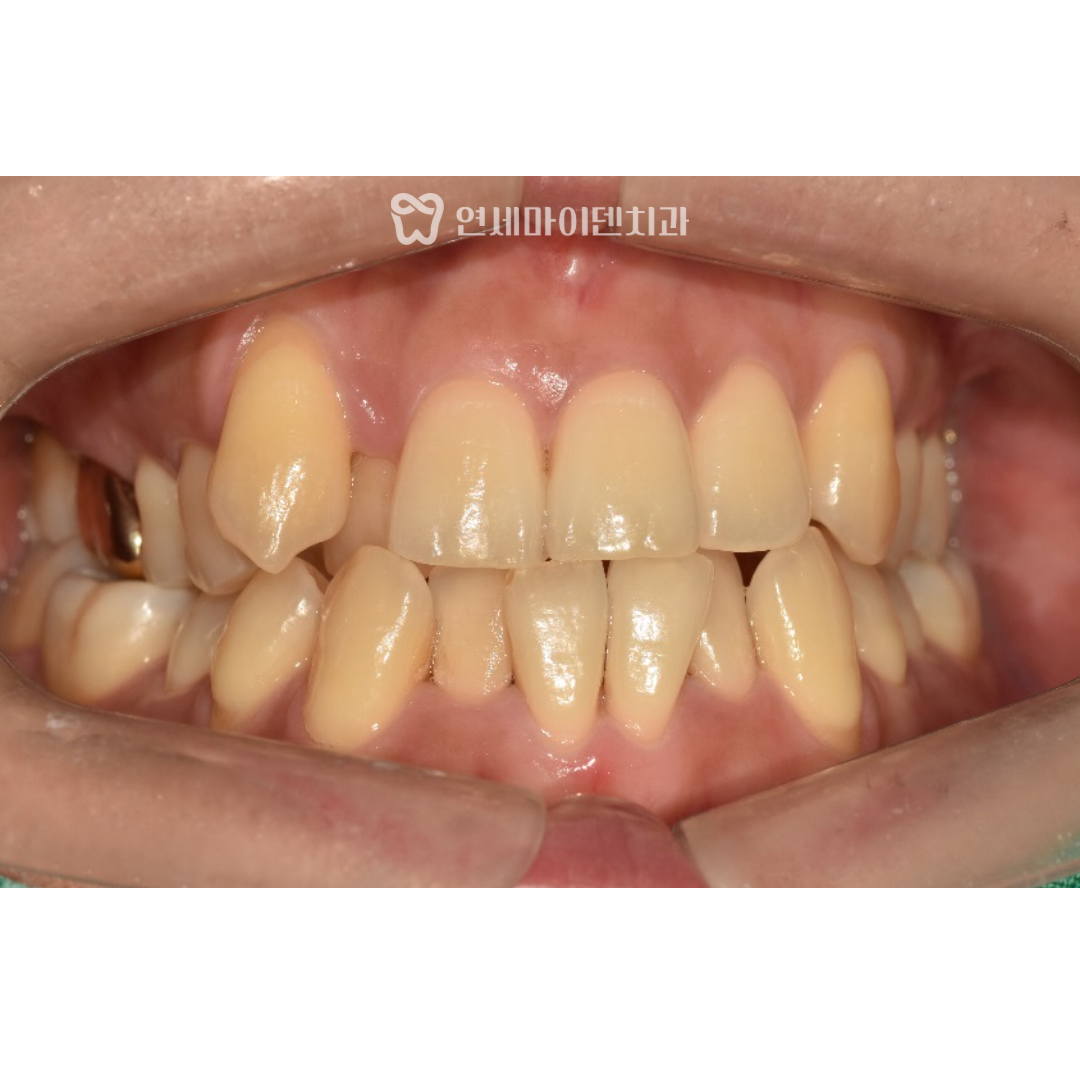

이 환자분은 30대 여성분으로

오른쪽 위 송곳니가 덧니로 나와있는 상태였고,

위쪽 앞니들이 겹쳐져 있었습니다.

특히 앞니 중심선이 맞지 않아서

전체적으로 삐뚤빼뚤한 치열을 가지고 계셨습니다.

여성분이시다보니 가지런하지 못한 치열이 콤플렉스라서

환하게 웃지 못했고, 성인 치아교정을 위해 저희 병원에 오셨습니다.